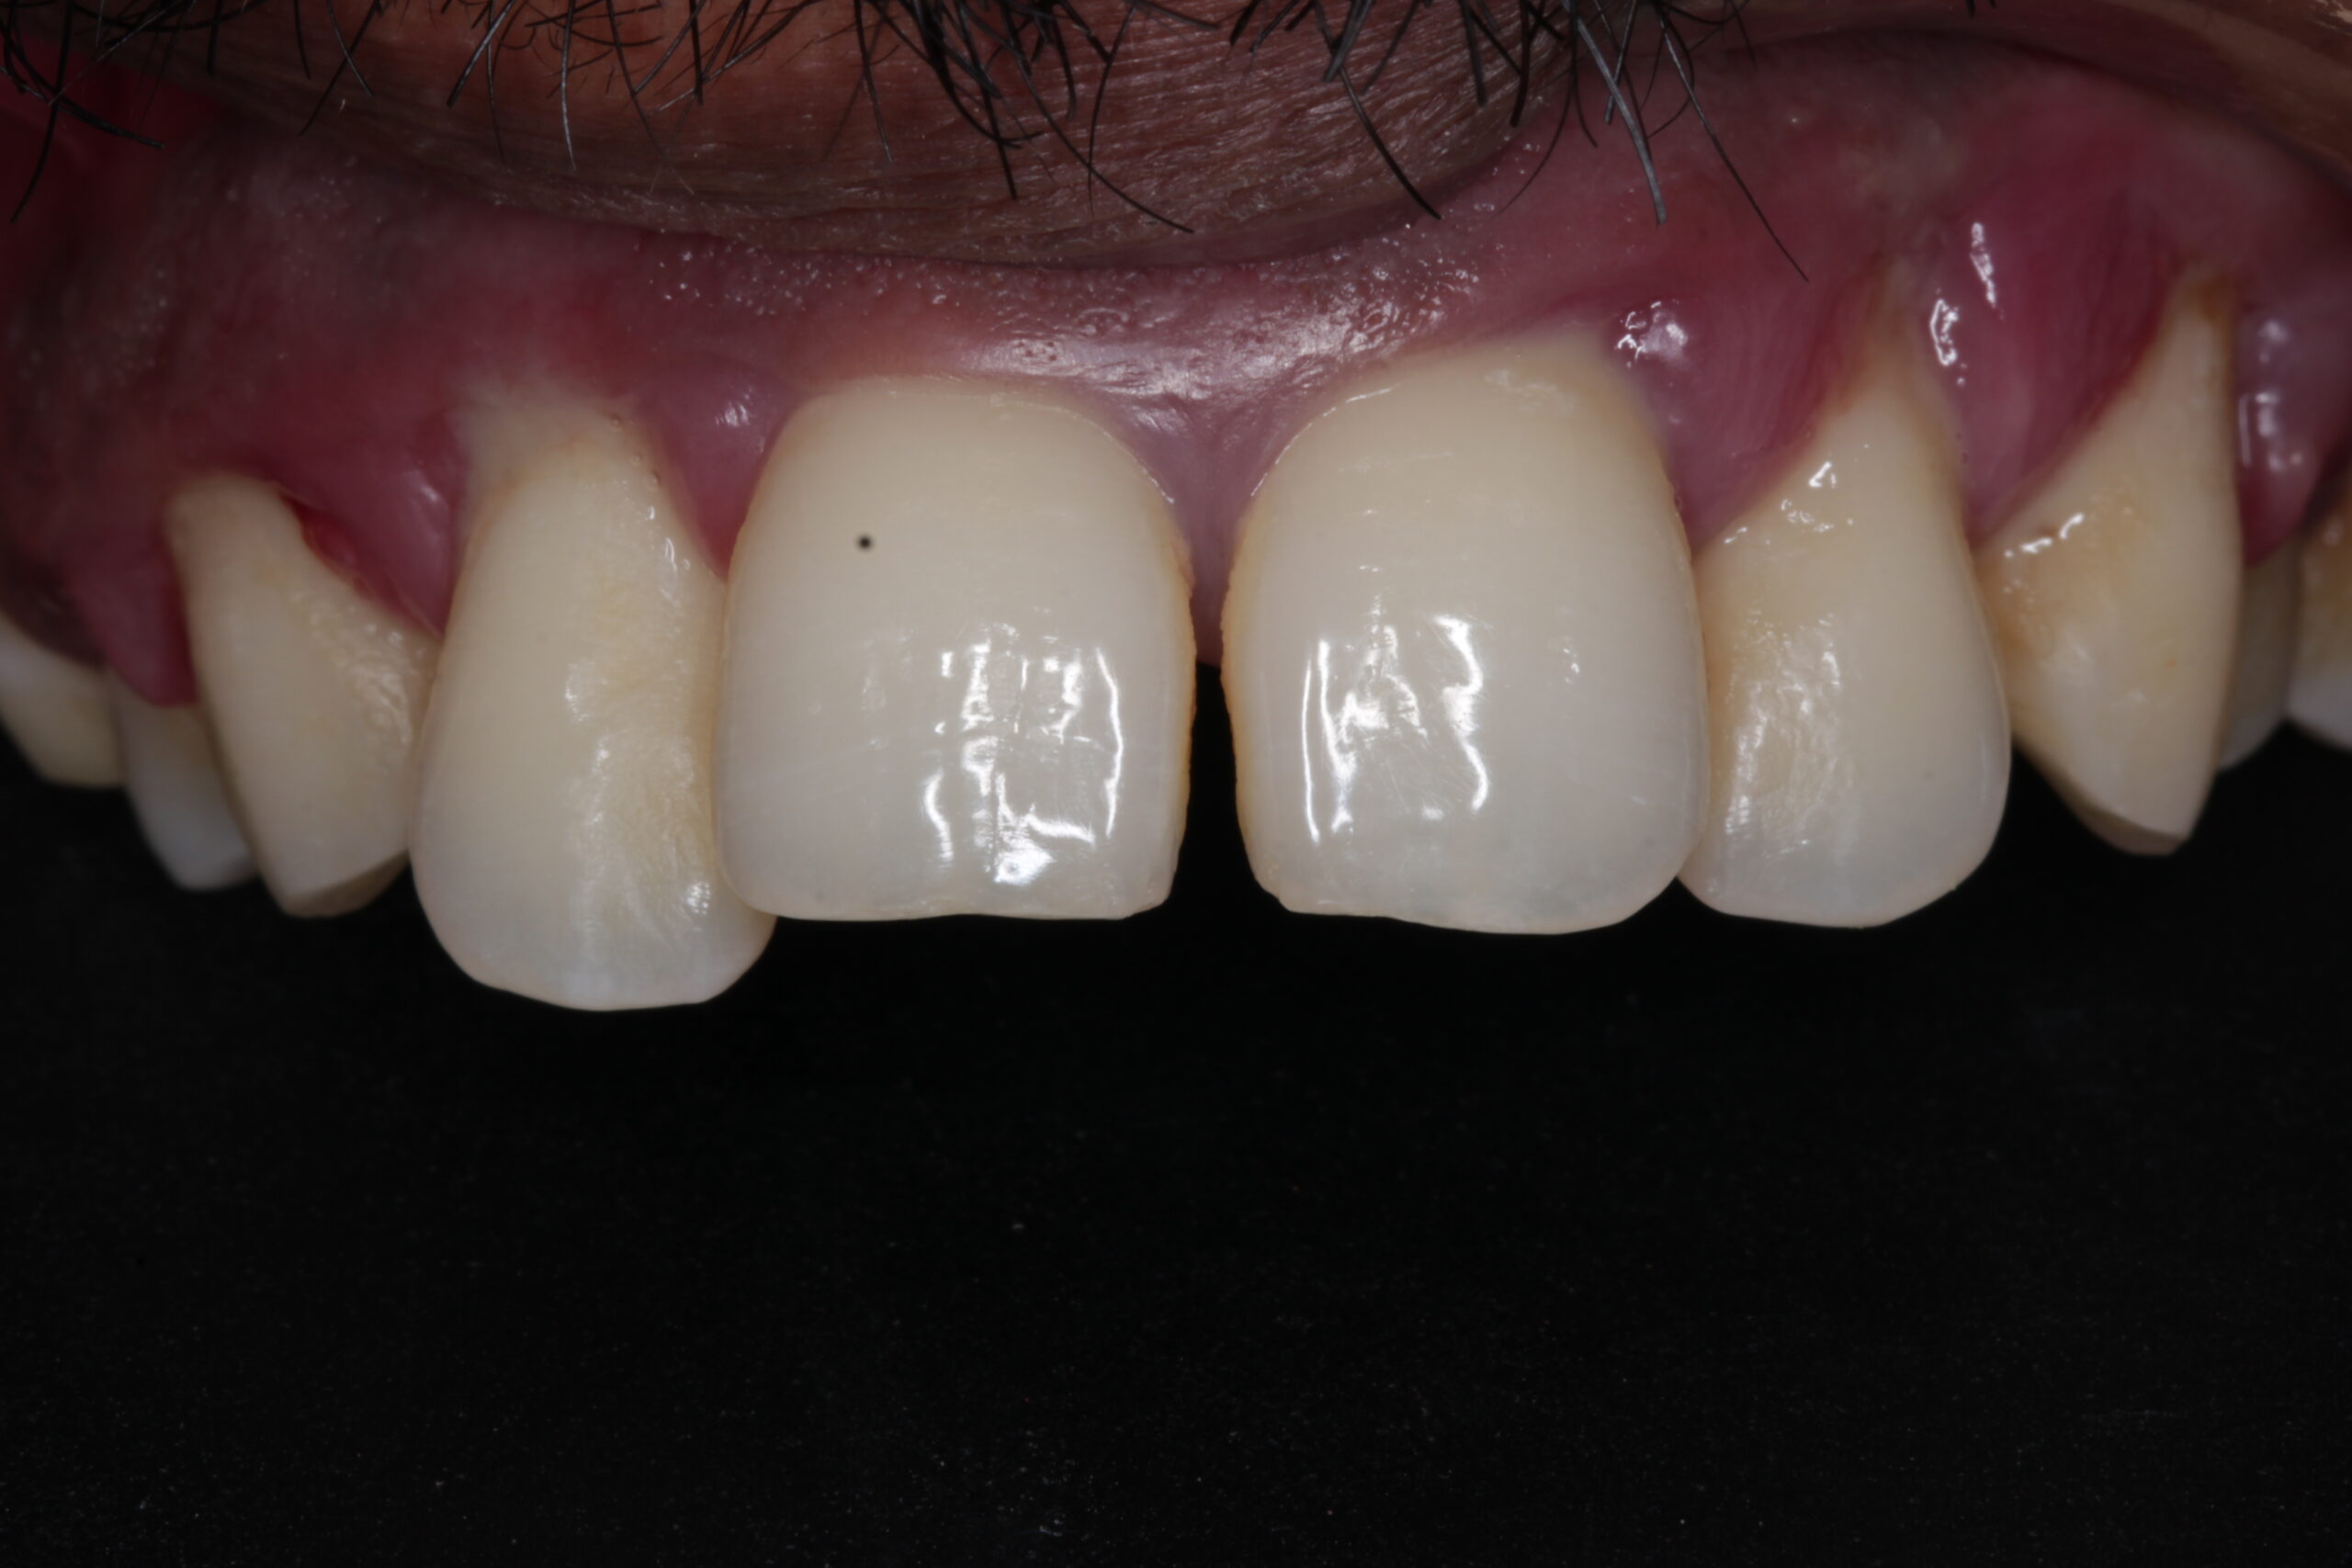

Protect Your Smile with Expert Gum Care

Gum care involves maintaining the health and well-being of the gums, which are critical for supporting teeth. Healthy gums help to prevent tooth loss, gum disease, and other oral health problems. At Apple Dental Care, we offer several advanced treatments to ensure that your gums remain in excellent condition.

Healthy gums contribute to a beautiful smile, enhancing the overall look of your teeth.